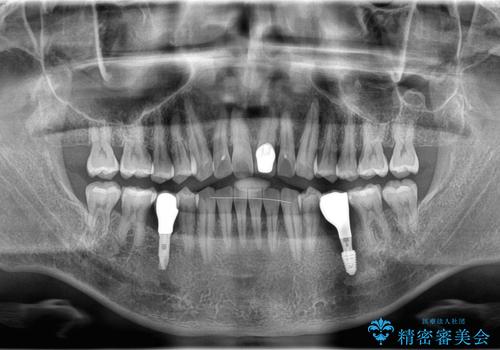

- 20年振りの来院で下顎左右5番にインプラント入れていた患者様です。

右下5番のインプラントは問題ありませんでしたが、左下5番のインプラントがインストール周囲炎に罹患している状態でした。

インプラントを抜去後、再びインプラントで治療を行いました。

20年以上振りのご来院でした。